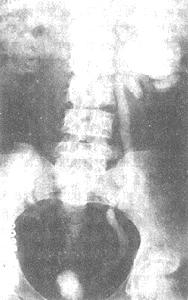

(2)延遲排泄性尿路造影

由於腎機能減退及造影劑為瀦留尿稀釋,故常規尿路造影時多不能顯示積水的影象。如能根據酚紅排出情況延遲X線攝片時間,可顯示腎積水。若有條件進行大劑排泄性尿路造影,結果更為滿意。

(3)腎穿刺造影術

由於膀胱病變嚴重,或輸尿管口狹窄,無法進行逆行腎盂造影;同時又因腎機能減退,排泄性尿路造影往往不顯影,如膀胱又無逆流時,腎穿刺造影是唯一可靠的診斷方法。這種方法一方面可根據抽得尿液的性質作診斷;另一方面可根據造影結果來鑑別是雙側腎結核抑為一側腎結核對側腎積水。

(4)膀胱回流造影

如有膀胱輸尿管逆流時可用膀胱回流造影術顯示腎和輸尿管的情況。檢查時最好用稀釋一倍的靜脈造影劑,並加入抗菌素預防上行性感染。